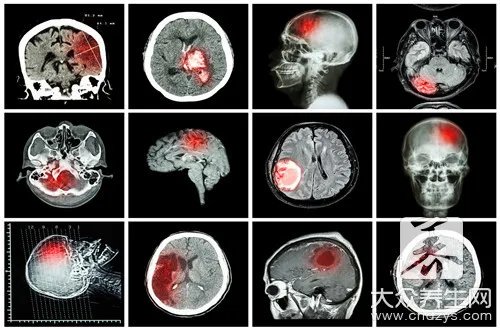

脑干梗塞是什么症状,它是需要我们来进一步去掌握的,那麼针对脊髓身体的管理中心具体指导,我们是更为需要了解有关它的一些症状,也有有关这种症状它的伤害。

1、临床医学上普遍的有关脊髓的堵塞那主要是有脑血栓也有脑栓塞而造成的。

脑血栓是因为主动脉的狭小,也有官腔内的慢慢产生了静脉血栓,而最后造成 了堵塞主动脉即而导致了脑梗塞。

脑栓塞的产生的原因,它是因为血液中有被称作栓子的出现异常物质,而堵塞了主动脉即而造成的。